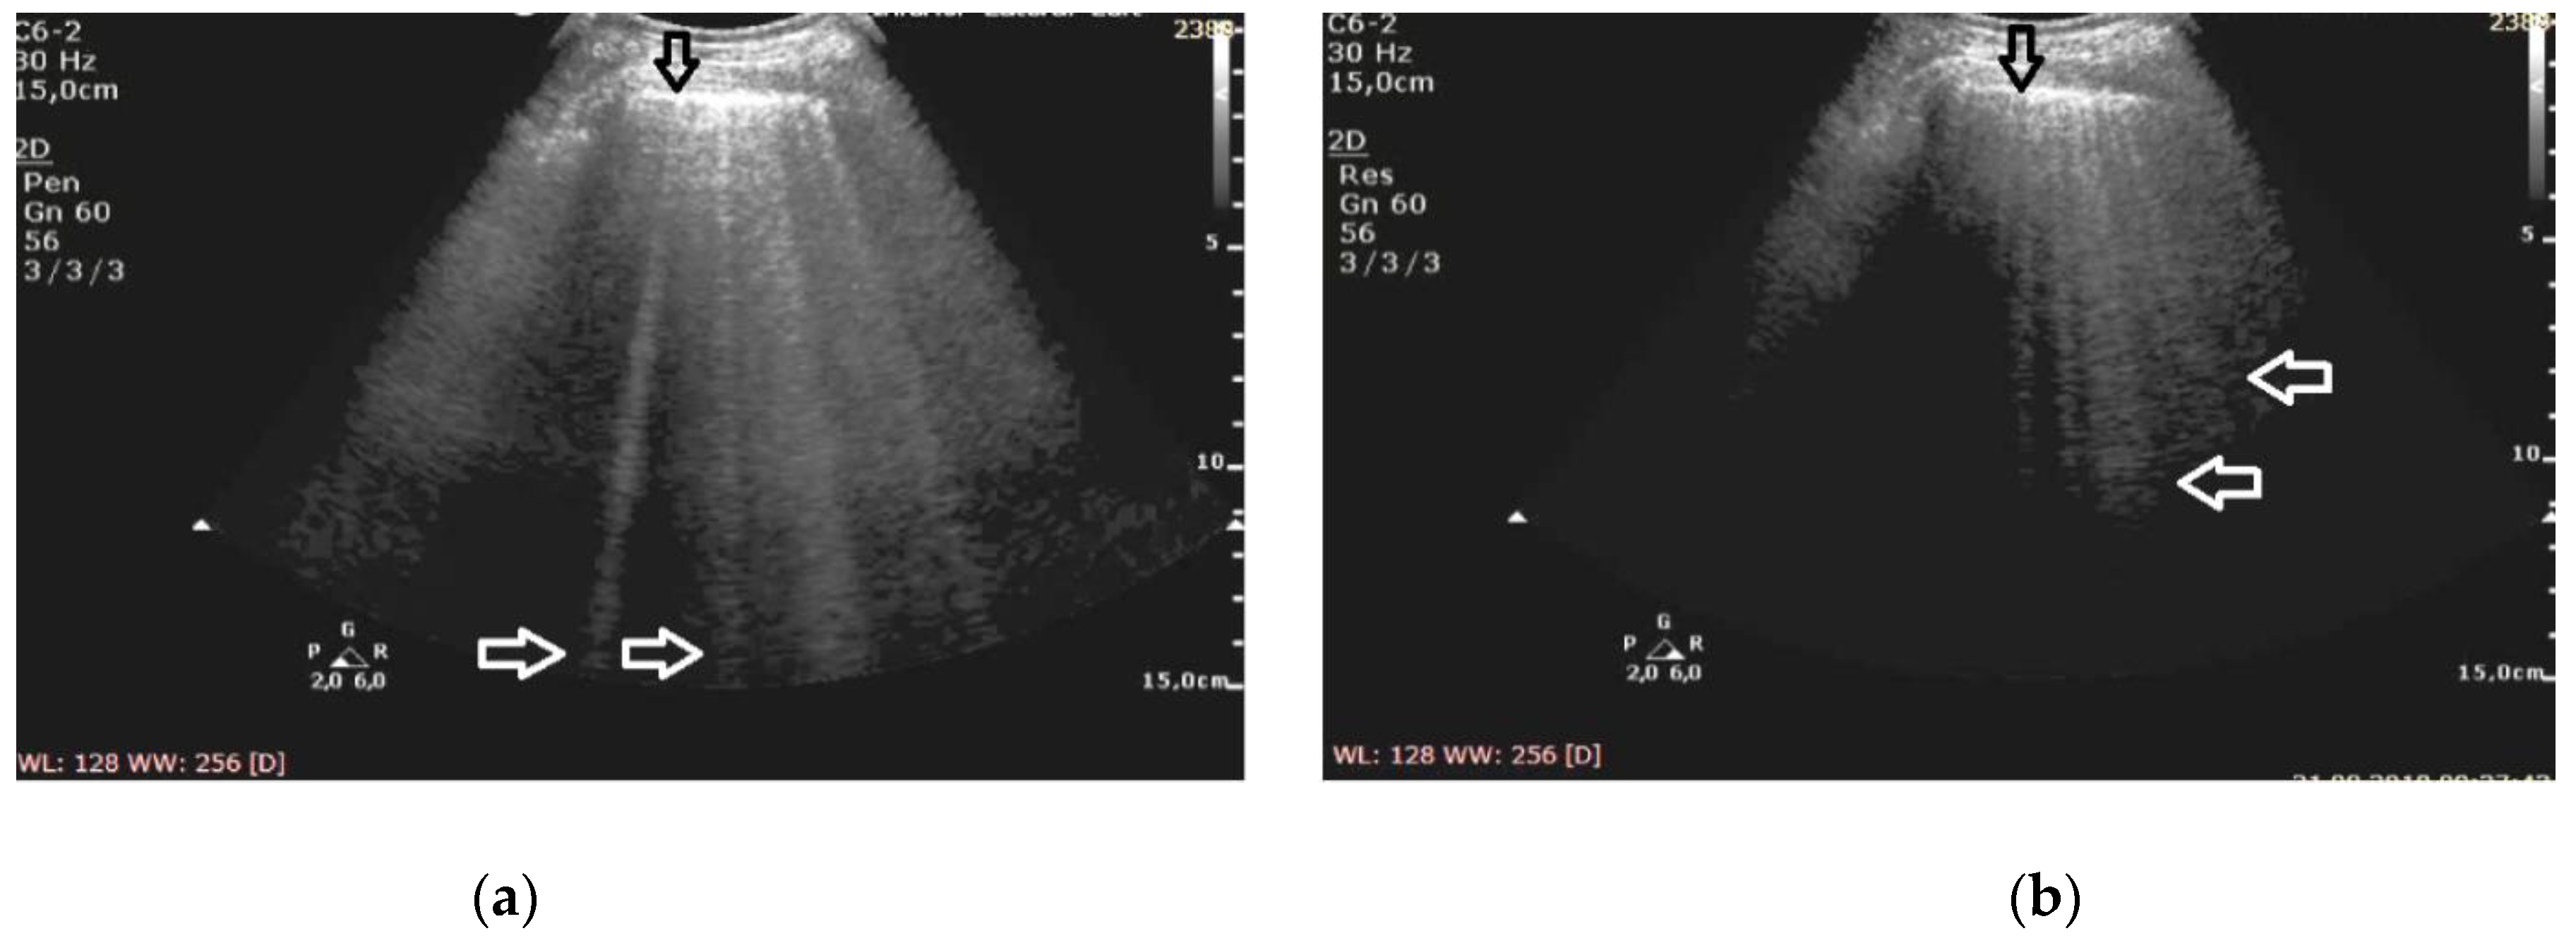

At the frequency of 6 MHz, cineloops recorded for patients with ILD presented Z-lines in 62% of the evaluated points and B-lines in 13%, whereas in 10% of the examined points the findings were mixed (Figure 1).

Figure 1. Pulmonary fibrosis; (a) B-lines at 2 MHz (white arrows), irregular pleural line (black arrow), (b) Z-lines at 6 MHz (white arrows), irregular pleural line (black arrow).